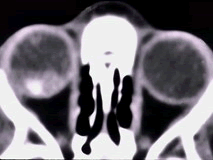

辅助检查中最有意义的发现是(如图)()

-